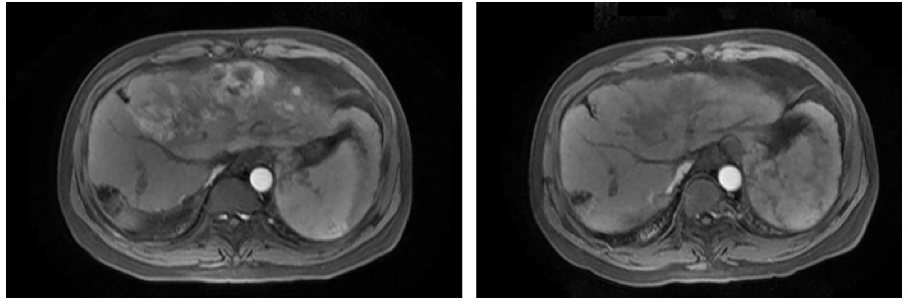

2021年11月3日MR显示,肝癌综合治疗后,病灶较前明显缩小,大小约12.2cm×8.1cm,门静脉左支癌栓;肝门区淋巴结显示;肝硬化(图6)。

图6. 2021年11月3日复查MR

复查评估显示,肝内病灶较前明显缩小,肿瘤标记物显著降低,mRECIST 标准:疾病缓解(PR)(图7)。

图7. MR复查评估